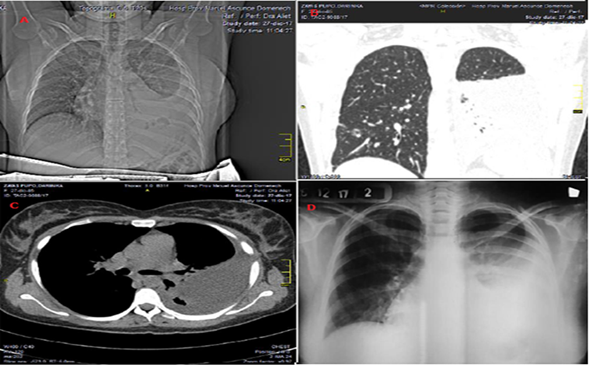

Luego ante la evolución no satisfactoria de la enferma se decide realizar tomografía axial computarizada simple de pulmón, que informa: presencia de moderada cuantía de líquido en cavidad pleural izquierda que provoca colapso parcial del pulmón en su lóbulo inferior con desplazamiento del mediastino y sus estructuras (tráquea y grandes vasos) hacia la derecha (Fig. 1).

Se plantea el diagnóstico de empiema pleural subagudo por lo cual se realiza pleurotomía mínima baja y se extrae aproximadamente 500 ml de líquido purulento espeso.